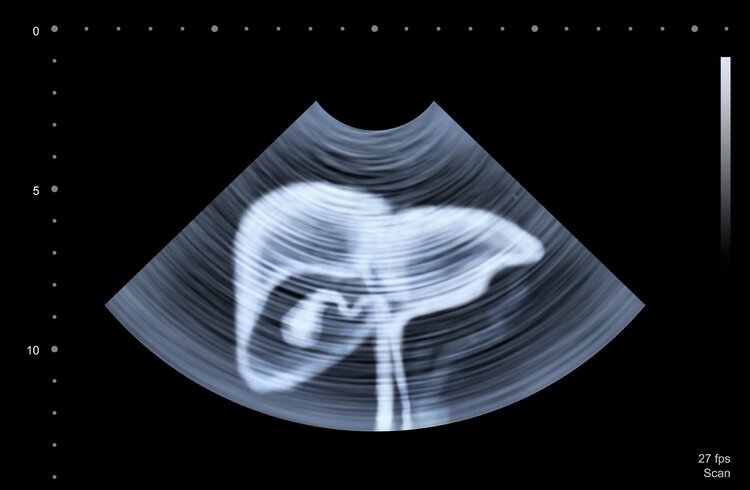

筛查建议:定期进行血清甲胎蛋白 (AFP) 和肝脏 B 超检查,一般6个月筛查一次。